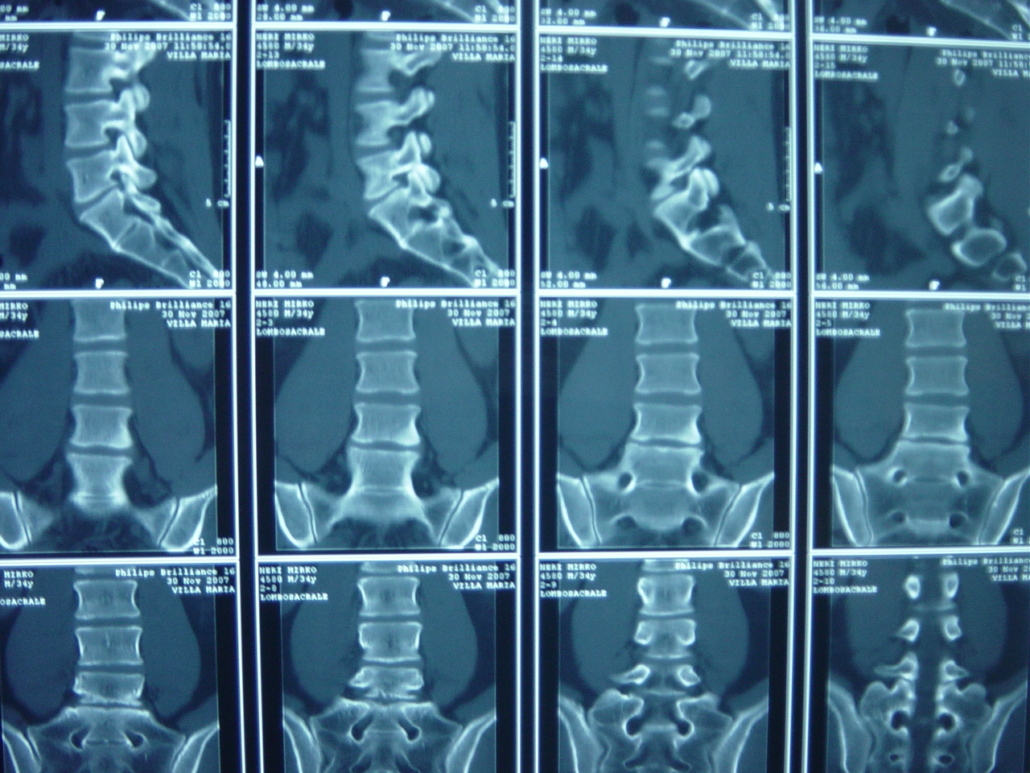

Lastra alla schiena. È bene rammentare che con la radiografia della colonna lombosacrale non si possono fare diagnosi di ernia del disco, ma solo escludere altre malattie con sintomi simili (tumori, forme infiammatorie, fratture, malformazioni ecc) La TAC e la RM sono pressoché sovrapponibili in termini di valore diagnostico per il medico;. Devo fare la lastra alla schiena!?. Ormai la schiena e il sedere mi fanno abbastanza male e ho solo 17 anni Grazie a tutti.

L’esame radiografico della colonna vertebrale completa (in toto) è un esame radiologico condotto mediante l’utilizzo di raggi X che riescono ad attraversare il corpo umano e a imprimersi in modo fotograficoIl risultato è un’immagine che evidenzia in modo differente ossa e scheletro rispetto ai tessuti molli (muscoli e pelle. Ho un problema alla schiena,una ernia L4L5 e responsabile di compressione sull’emergenza radicolare di L5 bilaterale Mi hanno mandato a fare un po’ di ciclo di ginnastica posturale e rinforzo della muscolatura addominale e anche di dimagrire,ma io al camminare sento un dolore fortissimo dalla coscia fino alla caviglia. Come Determinare se Hai la Polmonite La polmonite è un'infezione che si sviluppa nelle sacche d'aria all'interno dei polmoni Può essere causata da batteri, virus o funghi che iniziano a moltiplicarsi Questa malattia è più pericolosa per.

Attualmente la radiologia generale è interamente digitale, con grandi vantaggi relativi principalmente alla conservazione delle immagini, alla quasi totale scomparsa delle pellicole con riduzione drastica dell’inquinamento ambientale, ed alla possibilità di consulti ed esecuzioni di esami a distanza (teleradiologia) Prestazioni eseguite in Radiologia Esami contrastografici con tecnica. In questo articolo hai visto tutte le cause alla base della sensazione di tensione e contrattura muscolare costante Hai quindi capito perché puoi sentire i tuoi muscoli della schiena e delle spalle sempre contratti e tesi come se fossero delle corde di violino. Quali sono le alternative?.

Risonanza Magnetica Lombo Sacrale